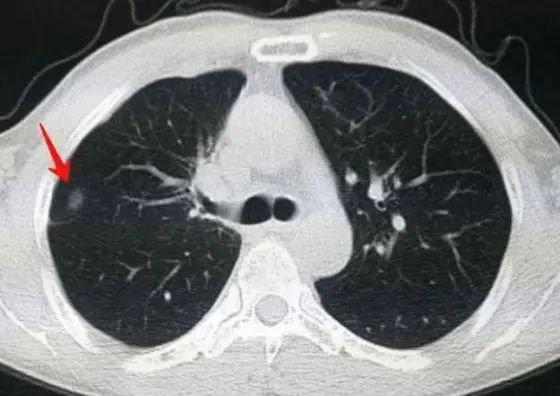

实际上,肺部结节并不是儿童胸部影像学检查中的罕见表现,随着CT的广泛应用,肺结节的检出率逐步提高,它指的是被肺实质包围的,直径不超过3cm的不透明阴影。但由于肺结节表现各异,临床诊疗缺乏统一的儿科指南,使得肺结节的鉴定和评估成为一个难题。

根据结节病灶密度可以分为实性结节(solid nodule,SN)、部分实性结节(part solid nodule,PSN)和磨玻璃样结节(ground glass nodule,GGN)三型。其中,恶性概率从高到低依次为PSN>GGN>SN。成人肺结节的病因复杂,各种感染及炎症、瘢痕、血管畸形、原发或转移性肿瘤均可引起,但现有的肺结节管理指南主要针对中老年人群,并不适合外推至儿童。